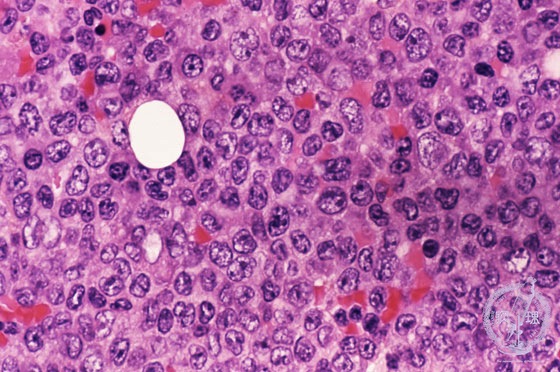

Microscopic image (H&E high power view): Myeloblasts composed of 95% of packed cells. Many of those have kidney-shaped nuclei.